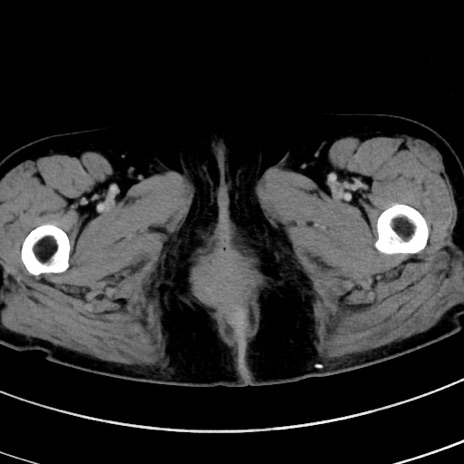

症例9(横断像)

【症例】 60歳代女性

【主訴】むかつき、みぞおちの痛み

【現病歴】3日前よりむかつきがあり、食事がとれない。

【既往歴】糖尿病

【身体所見】発熱なし、心窩部圧痛軽度あるも、腹膜刺激症状なし。

【データ】WBC 7400、CRP 1.92